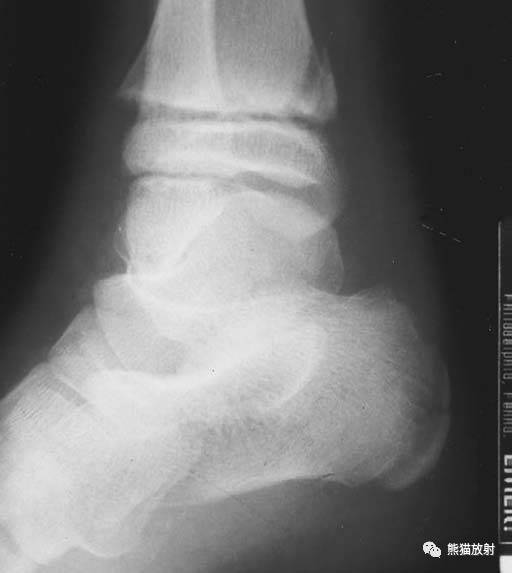

(上图)胫骨远端骺板变窄,同时可见并发的跟骨骨折。

Salter-Harris V型:由轴向压力导致的挤压伤,表现为骺板的明显扭曲或变窄。

第五型(V型) 骺板挤压性损伤,少见,占骨骺损伤的1%。由于严重暴力损伤造成,相当于骺板软骨的压缩骨折,有学者指出此型损伤只发生在一个方向活动的关节,如膝关节和踝关节。由于软骨细胞严重损伤破坏或来自骨骺营养血管广泛损伤,导致骺板早闭和生长停止。逐渐出现骨骼变形和关节畸形 ,但早期X线表现常常为阴性结果,多在晚期发生生长障碍时才能作出诊断。